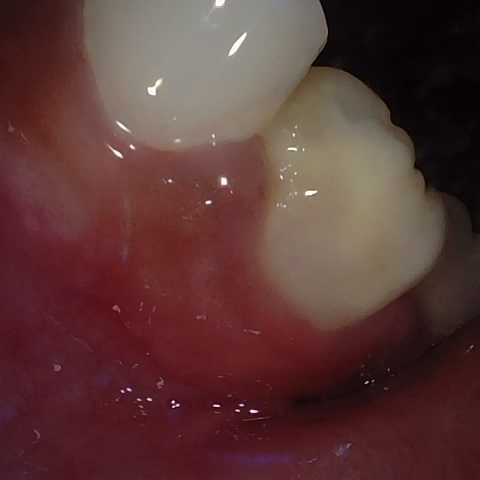

Annotated as "Good"